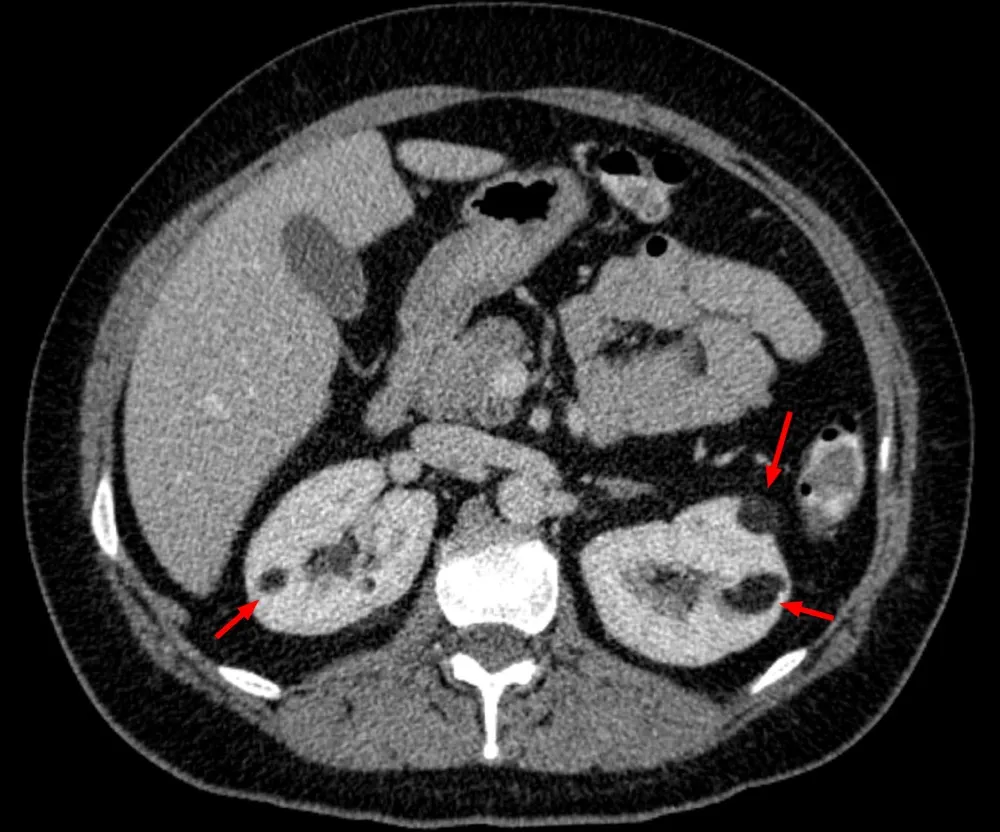

Uma causa incomum de hematúria glomerular intermitente!

Uma causa incomum de hematúria glomerular intermitente!

Hematúria pós infecção, caso clínicos para auxiliar no entendimento de causas glomerulares comuns e raras...